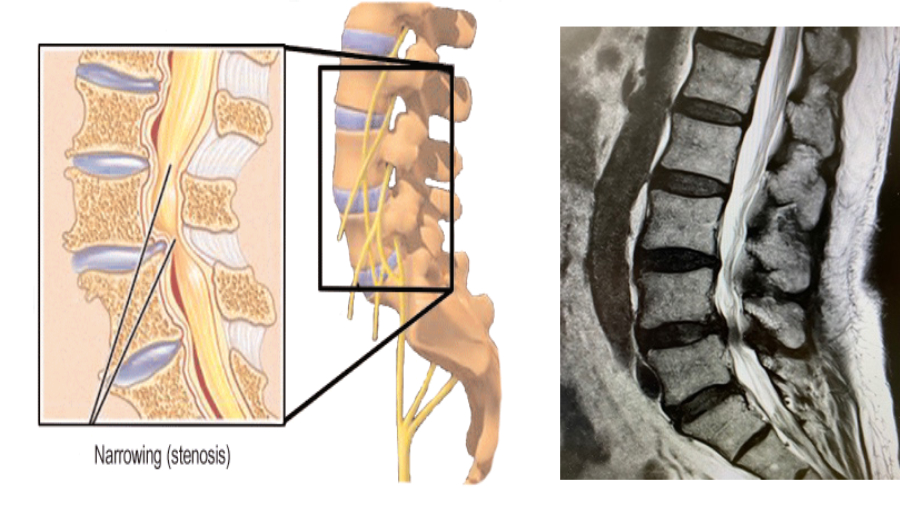

Spinal Stenosis Grades and Treatment Options Premia Spine What Is Pid Lumbar Spine Learn about the causes, symptoms, diagnosis, and treatment options for pivd. What is a slipped disc? There are two processes that can. Learn about the symptoms, causes, types, stages, diagnosis, treatment. A slipped disc is when a soft cushion of tissue between the bones in your spine bulges outwards. Pivd is a common cause of back and neck pain, caused. What Is Pid Lumbar Spine.

Symptoms of Severe Spinal Stenosis of L4L5 Premia Spine What Is Pid Lumbar Spine Learn about the causes, symptoms, diagnosis, and treatment options for pivd. A slipped disc is when a soft cushion of tissue between the bones in your spine bulges outwards. Pivd is a common cause of back and neck pain, caused by a herniated disk that compresses a nerve. Pivd stands for prolapsed intervertebral disc, a condition that affects the spine. What Is Pid Lumbar Spine.